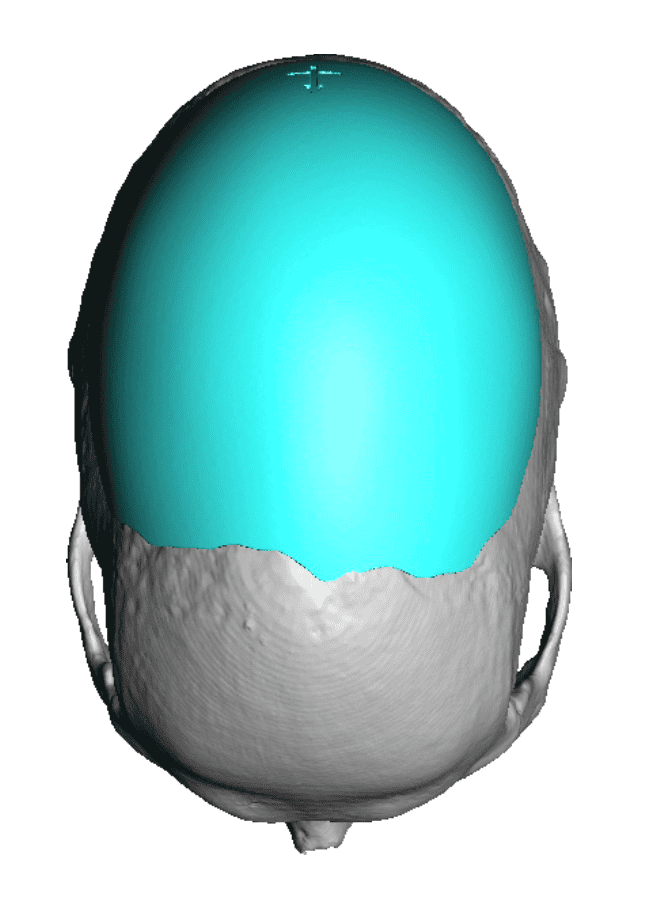

Severe narrowing skull deformity from prior sagittal craniosynostosis repair as an adult.

Complete replacement of entire skull by a custom implant with temporal fat injections.

Severe narrowing skull deformity from prior sagittal craniosynostosis repair as an adult.

Complete replacement of entire skull by a custom implant with temporal fat injections.